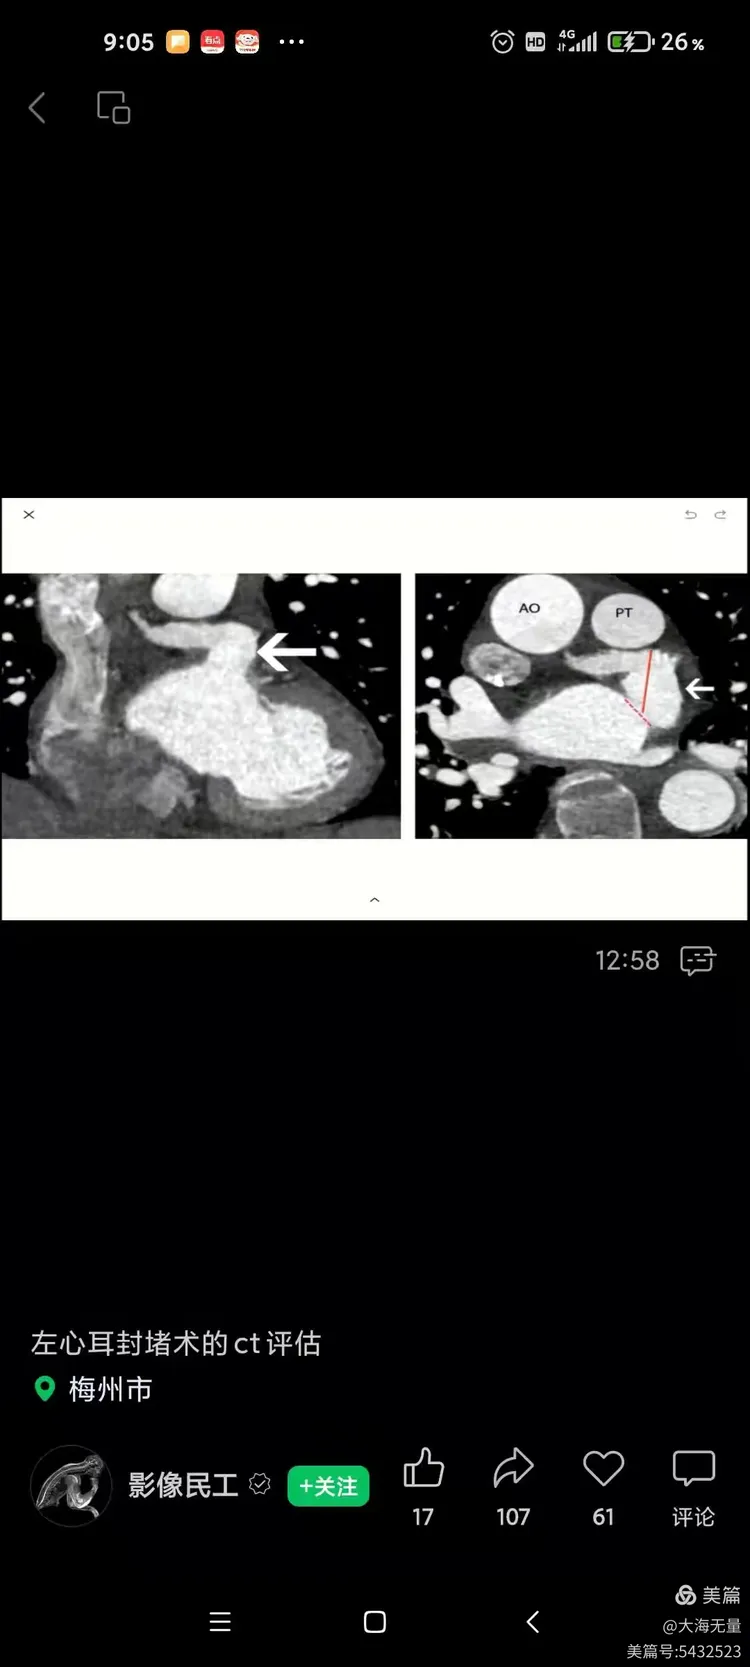

左心耳封堵术后ct表现

心脏ct三维分析在简化式左心耳封堵术中的应用研究